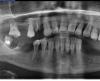

Bier Опубликовано 15 февраля, 2011 Поделиться Опубликовано 15 февраля, 2011 в максимально удобном варианте вам потребуется 14 имплантатов и 28 коронок. выкладывайте ортопантомограмму, какая есть. Через полгодика надо будет делать КТ и выбирать конструкцию. Ссылка на комментарий

Harmonie Опубликовано 17 февраля, 2011 Автор Поделиться Опубликовано 17 февраля, 2011 (изменено) Доброго времени суток.Посмотрите пжлста. Изменено 17 февраля, 2011 пользователем Harmonie Ссылка на комментарий